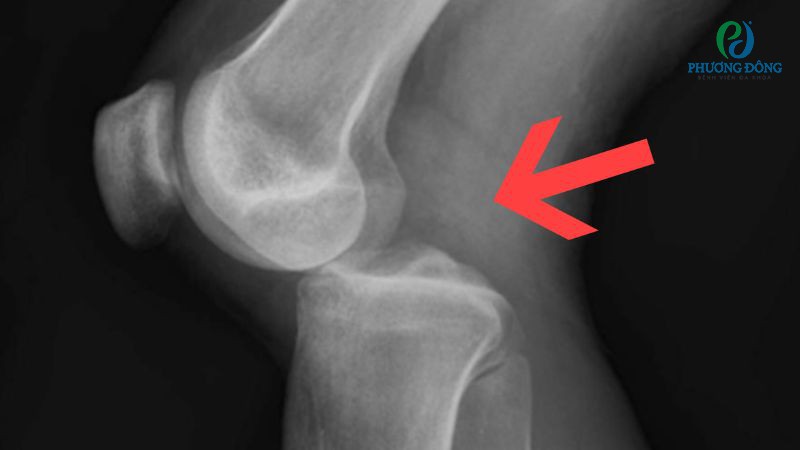

Gãy xương vùng khớp gối

Gãy xương vùng khớp gối cũng là một dạng chấn thương đầu gối thường gặp, có thể xảy ra ở một hoặc cả ba loại xương đùi, xương chày và xương bánh chè. Đường gãy nếu ảnh hưởng vào mặt khớp có thể làm mất sự linh hoạt khi vận động, gây cứng khớp, mất chức năng nếu không được chẩn đoán và điều trị kịp thời.

Nếu nhận thấy các biểu hiện dưới đây, người bệnh cần nhanh chóng đến bệnh viện thăm khám và can thiệp:

- Đau nhói tại vùng xương bị gãy.

- Sưng đầu gối, bầm tím vùng da xung quanh.

- Cơn đau tăng dần, khó có thể tự di chuyển.

- Xương đầu gối di động bất thường, nghe thấy tiếng lạo xạo.